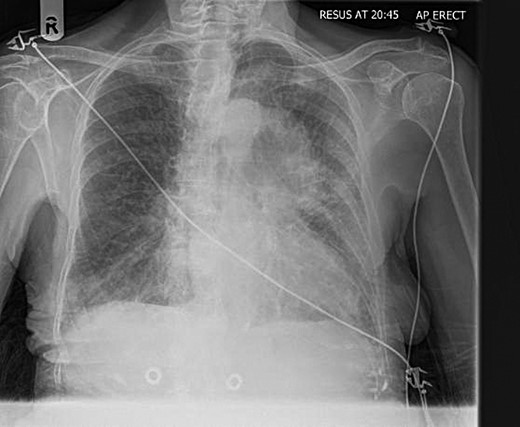

Her electrocardiogram showed ST segment depression in the lateral leads suggesting myocardial ischaemia. Her chest radiograph showed a well-circumscribed opacity appearing to arise to the left of the aortic arch (Fig. 1). Blood tests revealed haemoglobin of 13 g/dl.